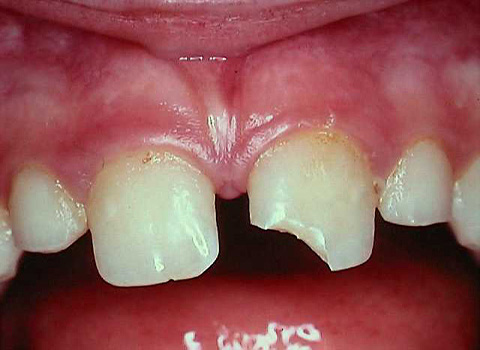

Get yourself treated with some of the best and finest dentists of the city visit our dental hospital.